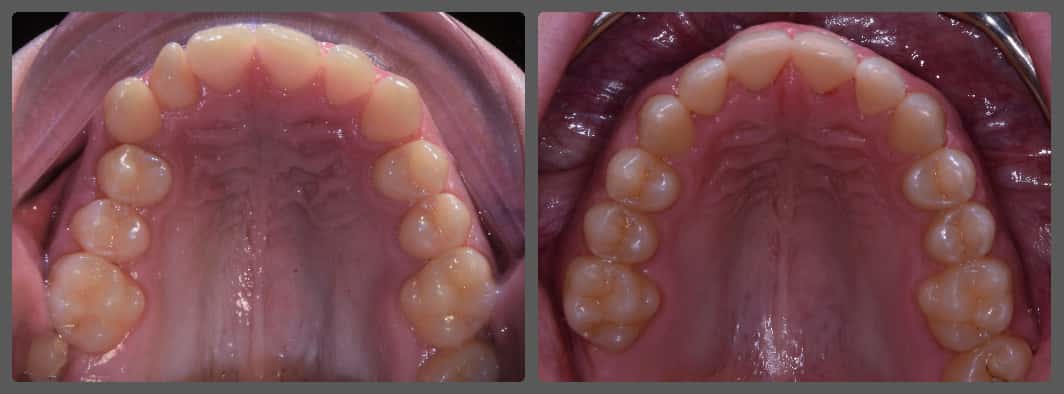

Balázs súlyos alsó torlódása miatt keresett fel magánrendelésemen. A diagnosztikus vizsgálatok során előbbin túl alsó-felső fogívszűkületet, valamint nyitott harapási hajlamot állapítottam meg. Kezelését Pitts21 alsó-felső rögzített fogszabályozó készülékkel kezdtük meg. A nyitott harapási hajlamot a hátsó fogakra helyezett harapásemelővel kontrolláltuk. A torlódott fogaknak tolórugóval és interproximális redukcióval teremtettünk helyet, és intermaxilláris gumihúzással tökéletesítettük a harapást. A fogszabályzó kezelés teljes időtartama alatt Balázs 110%-osan együttműködő volt, ezért 21 hónap alatt sikerült kiemelkedő végeredményt elérnünk.